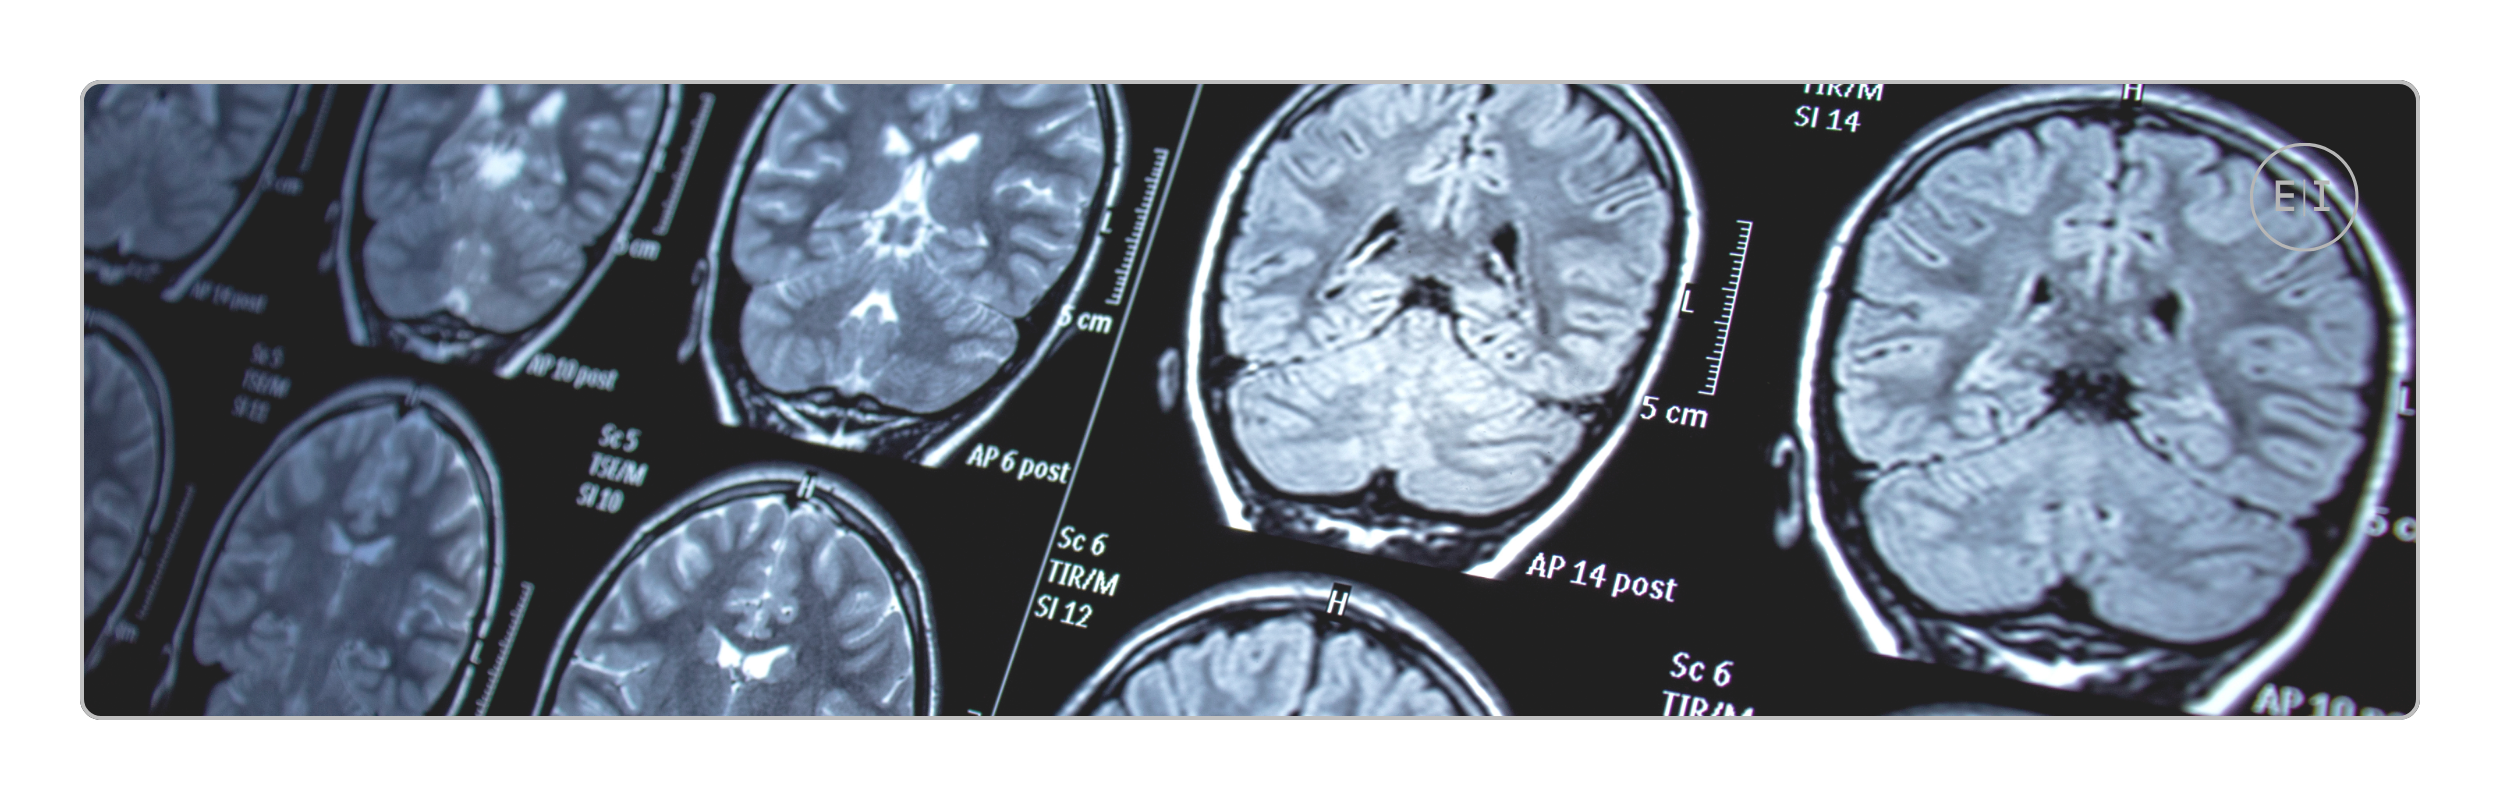

An MRI (Magnetic Resonance Imaging) is a medical imaging technique that uses a strong magnetic field and radio waves to create detailed images of the organs and tissues in your body. The MRI machine is typically a large, tube-shaped magnet. You lie inside this tube during the scan. The strong magnetic field aligns the protons in the water molecules within your body. Radio waves are then emitted, temporarily knocking these protons out of alignment. As the protons realign, they release signals that are detected by the MRI scanner. These signals are processed by a computer to create cross-sectional images of the body.

Sometimes, a contrast material (often called a contrast agent or MRI dye) is injected intravenously during an MRI scan. This contrast material typically contains a substance called gadolinium. It enhances the visibility of certain internal structures because it alters the magnetic properties of nearby water molecules. The key benefits of using contrast in MRI include:

• Improved image clarity and detail: Contrast agents make specific tissues or abnormalities stand out more clearly against the surrounding tissues. This allows radiologists to see even subtle differences that might be missed on a non-contrast MRI.